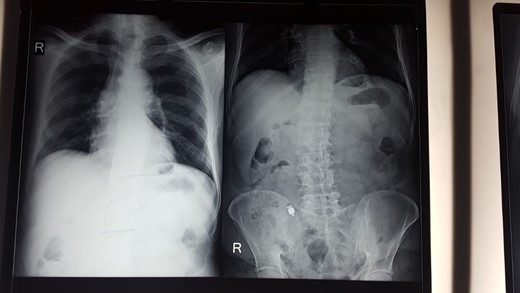

Abdominal X-ray showed the retained capsule in the right side of the abdomen (Fig. 1). Colonoscopy was normal.